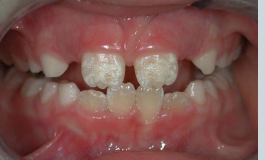

what is shown here?

enamel hypoplasia → not the same as hypo-mineralisation

Ameloblasts affected during development – less enamel formed Pits, grooves, thinning

enamel hypoplasia vs hypomineralisation

hypo-mineralisation is when you get the correct thickness of enamel but its softer and wears away faster

hypoplasia - structure is okay - but thinner, incomplete or pitted